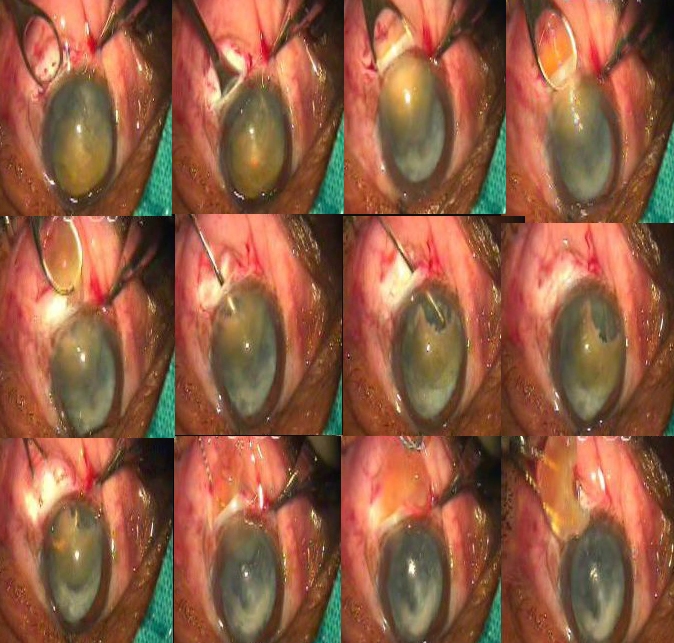

6 mm Intratunnel Phacofracture MSICS IN White cataract With A Large Nucleus With Floppy Iris

Intratunnel Phacofracture MSICS In Cataract With Pseudo Exfoliation And Non-Well Dilated HD (Unedited)

INTRATUNNEL PHACOFRACTURE: A NEW NUCLEUS MANAGEMENT TECHNIQUE OF MSICS